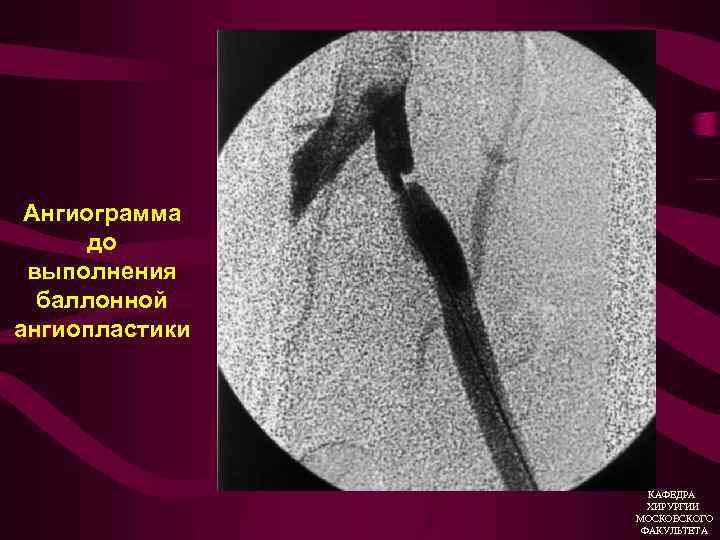

Эндоваскулярные вмешательства у больных с ХАН 1. Баллонная ангиопластика 2. Стентирование КАФЕДРА ХИРУРГИИ МОСКОВСКОГО ФАКУЛЬТЕТА

Ангиограмма до выполнения баллонной ангиопластики КАФЕДРА ХИРУРГИИ МОСКОВСКОГО ФАКУЛЬТЕТА

КАФЕДРА ХИРУРГИИ МОСКОВСКОГО ФАКУЛЬТЕТА